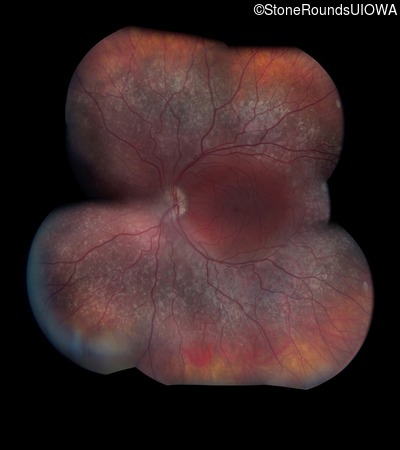

Age at visit: 18 years